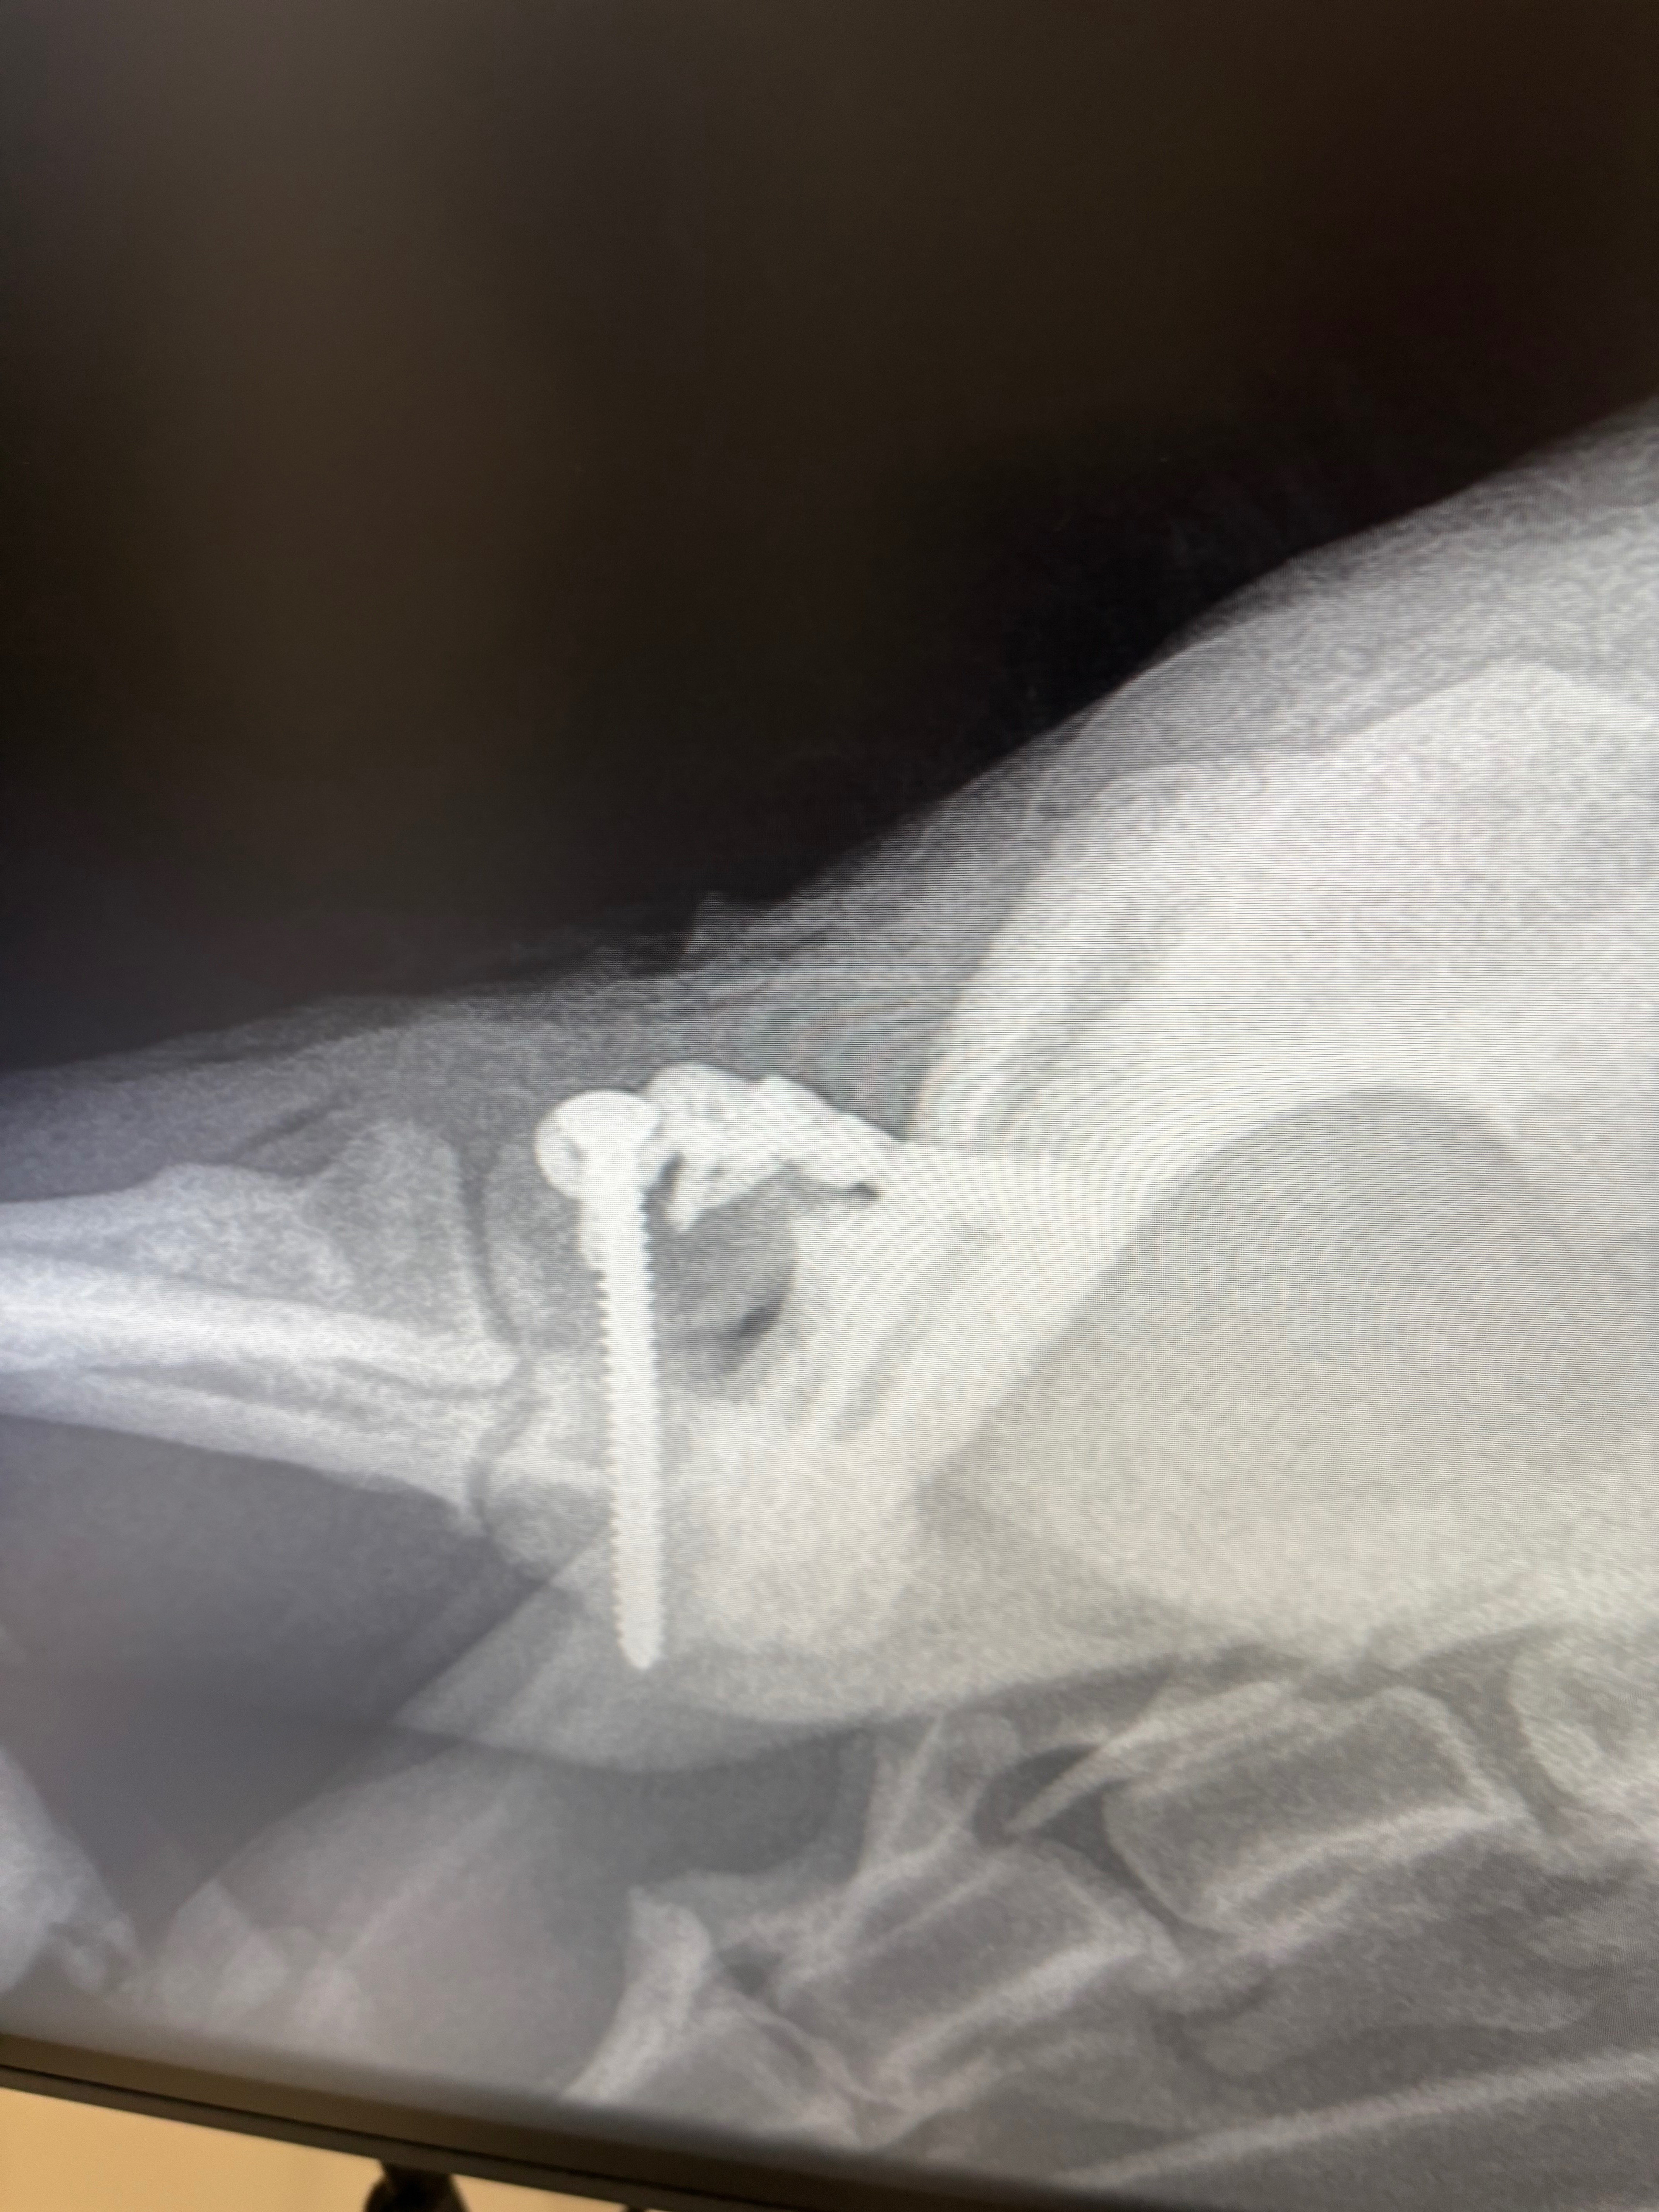

So yesterday evening (Saturday 6/9/25) my parents dog (Ralphie) had a serious accident out on his walk, which meant he was rushed to an out of hours vets where he’s had X-rays done which are showing he has a serious fracture on his elbow which means he will either need a big rebuild or leg amputated. So far the vets have said it’s going to cost £3.5k to keep him at the vets until Monday for his out of hours care and sedation/ pain relief . Then come Monday Ralphie will be taken back to his original vets where we can hopefully make a plan moving forwards. Either option is going to be highly expensive whichever route we go down, It would be be greatly appreciated if people could help donate toward Ralphie's Road to recovery ❤️‍ Even if you can just donate a couple of quid, every little helps and will make things a lot less stressful for the family at this hard time.

8/9/25- *update* Ralphie has been moved to Poole to see a specialist surgeon. He’s had Ct scans this morning which show he has a Y fracture, the surgeon has operated and done this kind of surgery before which was successful, so nice to hear some positive news. If all equipment is available today E.g (nuts, bolts, screws, plates) then surgery may go ahead today.